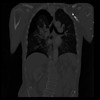

29 CUERPO,CE,Coronal,3.000,CUERPO,Coronal,